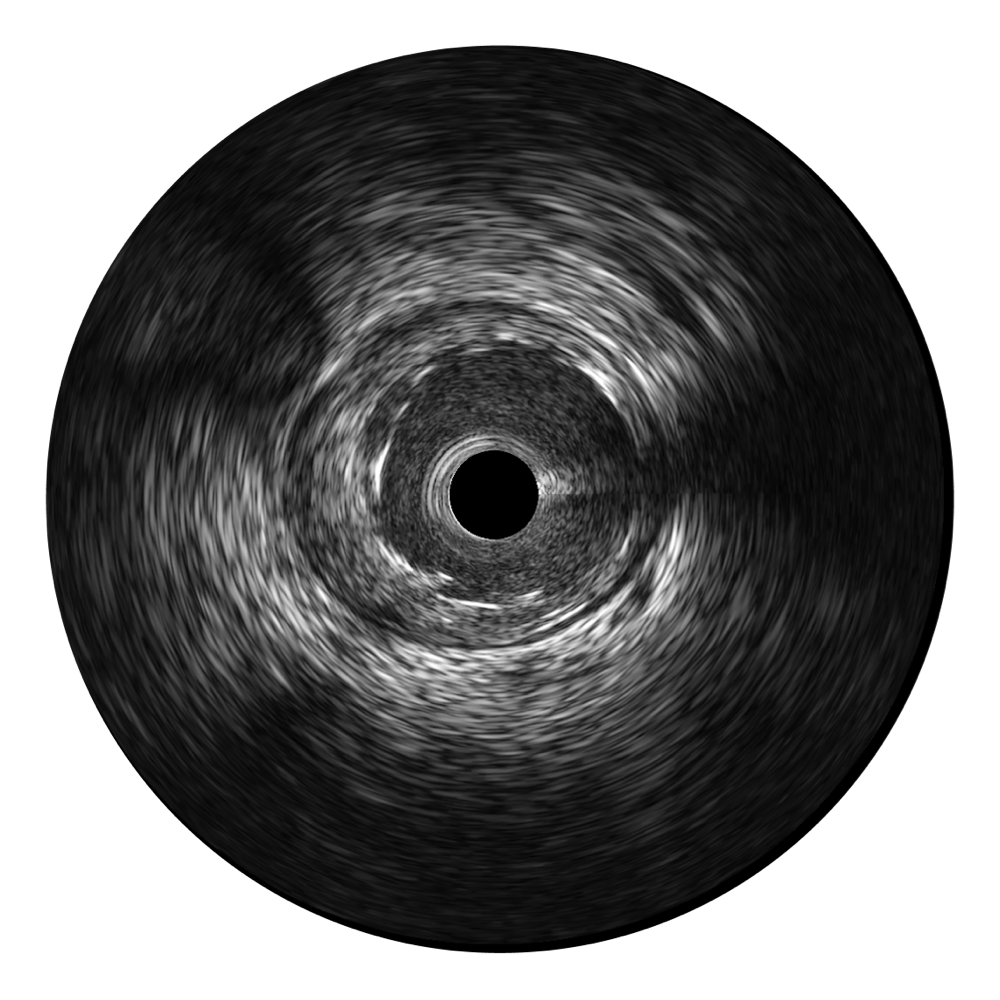

宽频成像,兼具高分辨力和更大穿透深度

环球UG官网超宽频成像技术覆盖20-80MHz1或20-90MHz2频率范围, 提供优异的分辨力同时也保证充足的穿透深度